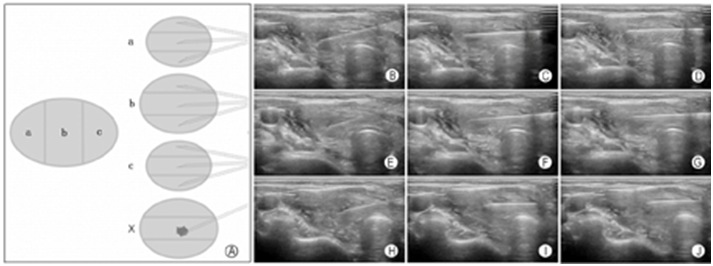

实践中,对于较大结节我们提倡采用基于"一针技术"的"9+X针道"穿刺模式,以最大化、全面化获取目标结节的穿刺标本。所谓"一针技术"是指穿刺针进入结节后,针尖仅在结节内作多次往复提插运动,穿刺针保持位于甲状腺内,不退出到腺体包膜外。在此基础上完成"9+X针道"穿刺取材。

"9+X针道"穿刺模式是指在甲状腺纵切面声像图上,将目标结节分为上、中、下三个分区,然后在横切面上对每个分区再分为前、中、后三个小分区,使用同一根穿刺针对9个小分区相继、连续穿刺取材,故整个病灶一次进针,便可从9个针道上吸取标本。"X"指不确定针数,若目标病灶内有微小钙化、血流信号异常丰富或无信号、弹性超声应变比值较大等特殊声像表现区域,则对其额外增加穿刺取材(targeted biopsy),吸取物涂布于另一张载玻片上,此即"9+X针道"穿刺模式的概念(图18)。

图18"9+X"针道穿刺模式 A:示意图;B~D:结节上三分之一段(a)的三个分区取材;E~G:结节中三分之一段(b)的三个分区取材;H~J:结节下三分之一段(c)的三个分区取材;

"9+X针道"穿刺模式在取材部位的全面性和均衡性、取材数量的充足性、取材质量的优化性、特征声像图表现对应性方面均体现出FNA当前的规范性和严谨性。